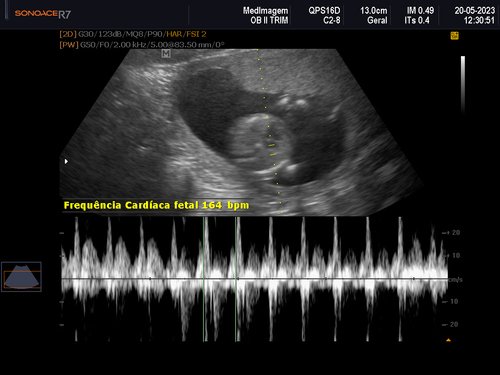

Eu tenho 27 anos estou grávida de 4 meses essa é a minha quarta gestação as minhas três últimas gestações eu perdi os bebês nunca consegui levar a gravidez adiante, eu quero muito conseguir levar essa, MINHA GRAVIDEZ É DE ALTO RISCO.

Uma amiga me deu a ideia de fazer uma vaquinha online, para conseguir fazer o tratamento no particular e o parto também, com ajuda de alguns amigos consegui arrecadar um valor e começar o tratamento no particular tive uma consulta com uma médica maravilhosa doutora Rochelle Hygino que na primeira consulta já me encaminhou para internação e para cirurgia, precisei fazer uma cerclagem no útero que é costurar o útero para segurar o bebê.